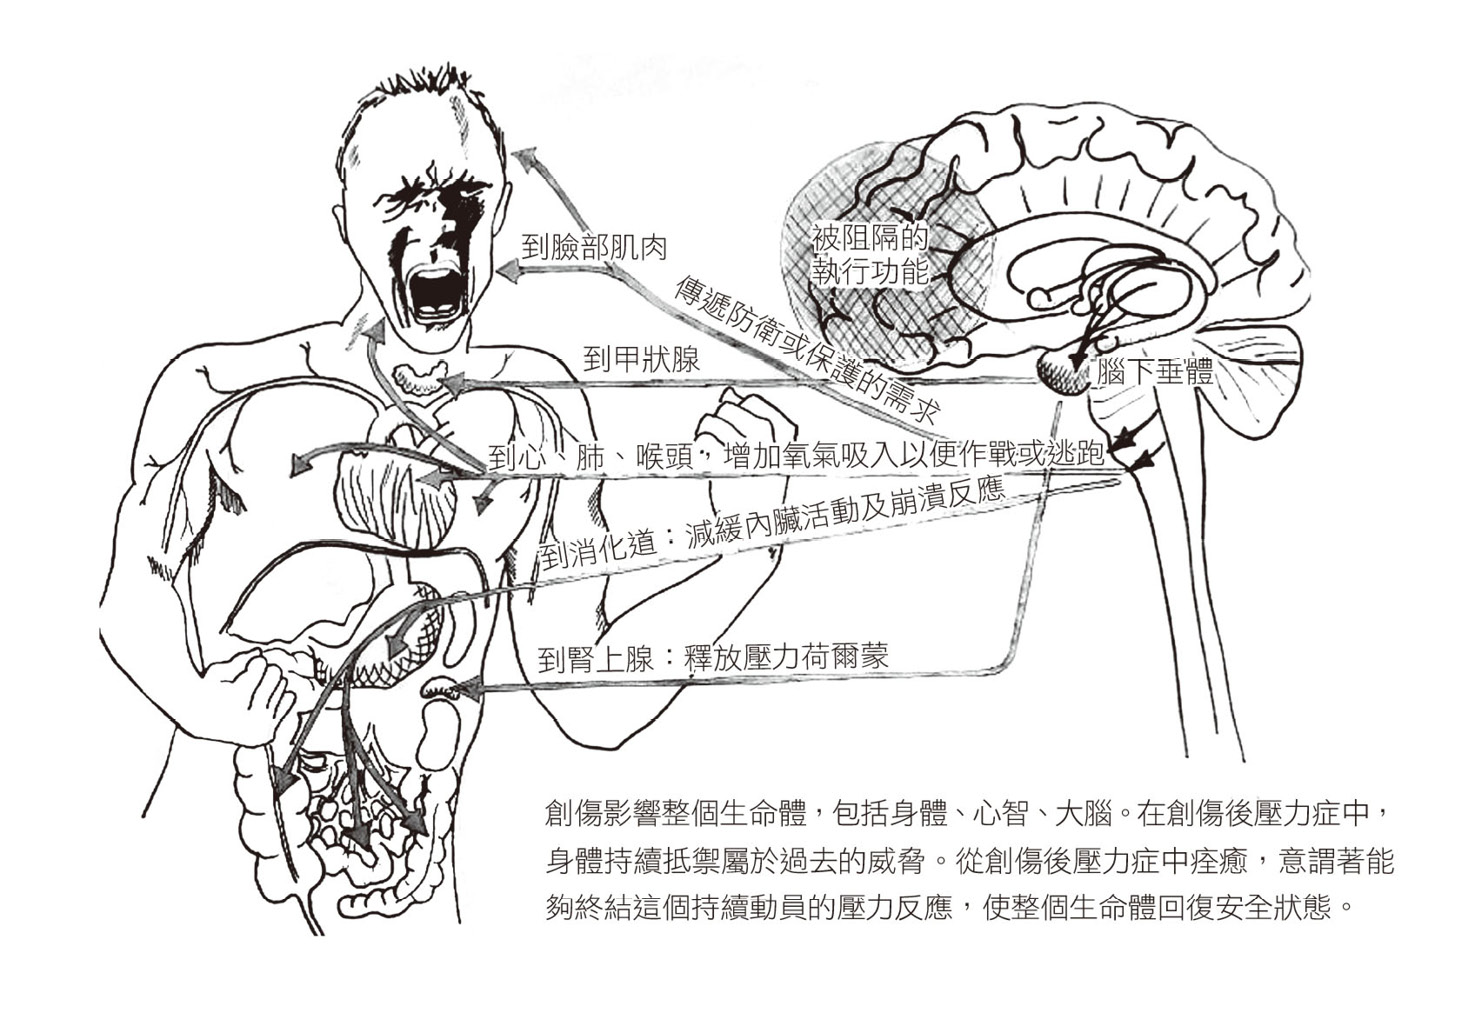

創傷發生後,倖存者用與過去不同的神經系統來體驗世界,這些人傾注所有精力壓抑內心的混亂,代價是無法自發參與自己的生活。他們試圖控制無法忍受的生理反應,卻因而導致各種身體症狀,包括纖維肌痛、慢性疲勞,以及其他自體免疫疾病。這說明瞭為何創傷治療必須納入完整的生命體,包括身體、心智與大腦。

上一頁的圖說明瞭整個身體面對威脅時的反應。

人腦中最古老的那一區已預先編寫好身體的逃跑計畫,腦部的警報系統一啟動,便會自動觸發。和其他動物一樣,組成大腦基本結構的神經和化學物質直接連向身體。原始腦接管身體的控制權後,會暫時關閉高階腦,也就是有意識的心智,並驅動身體逃跑、躲避、作戰,有時是楞住不動。等到我們完全意識到自己的處境,身體可能已經在動作了。倘若作戰/逃跑/驚呆的反應奏效,讓我們脫離危險,我們就會恢復內部平衡,且逐漸「恢復理智」。

假如正常的壓力反應因某些因素而受到封鎖,例如被劫持、囚禁,或其他無法採取有效行動的狀況,像是打仗、車禍、家庭暴力,或被強暴時,大腦仍會持續分泌壓力荷爾蒙,腦部的電流迴路也會持續無效地活躍。2實際的壓力事件結束很久之後,大腦可能仍會持續發出信號,不斷通知身體逃離某個早已不存在的威脅。一八八九年,法國心理學家皮耶.賈內發表了第一篇關於創傷壓力的科學研究3,我們從此瞭解創傷倖存者傾向「從事件發生後一直持續採取行動,或徒勞地試圖行動」。能夠行動,並做出一些事來保護自己,是決定恐怖經驗是否會留下長期傷痕的關鍵。